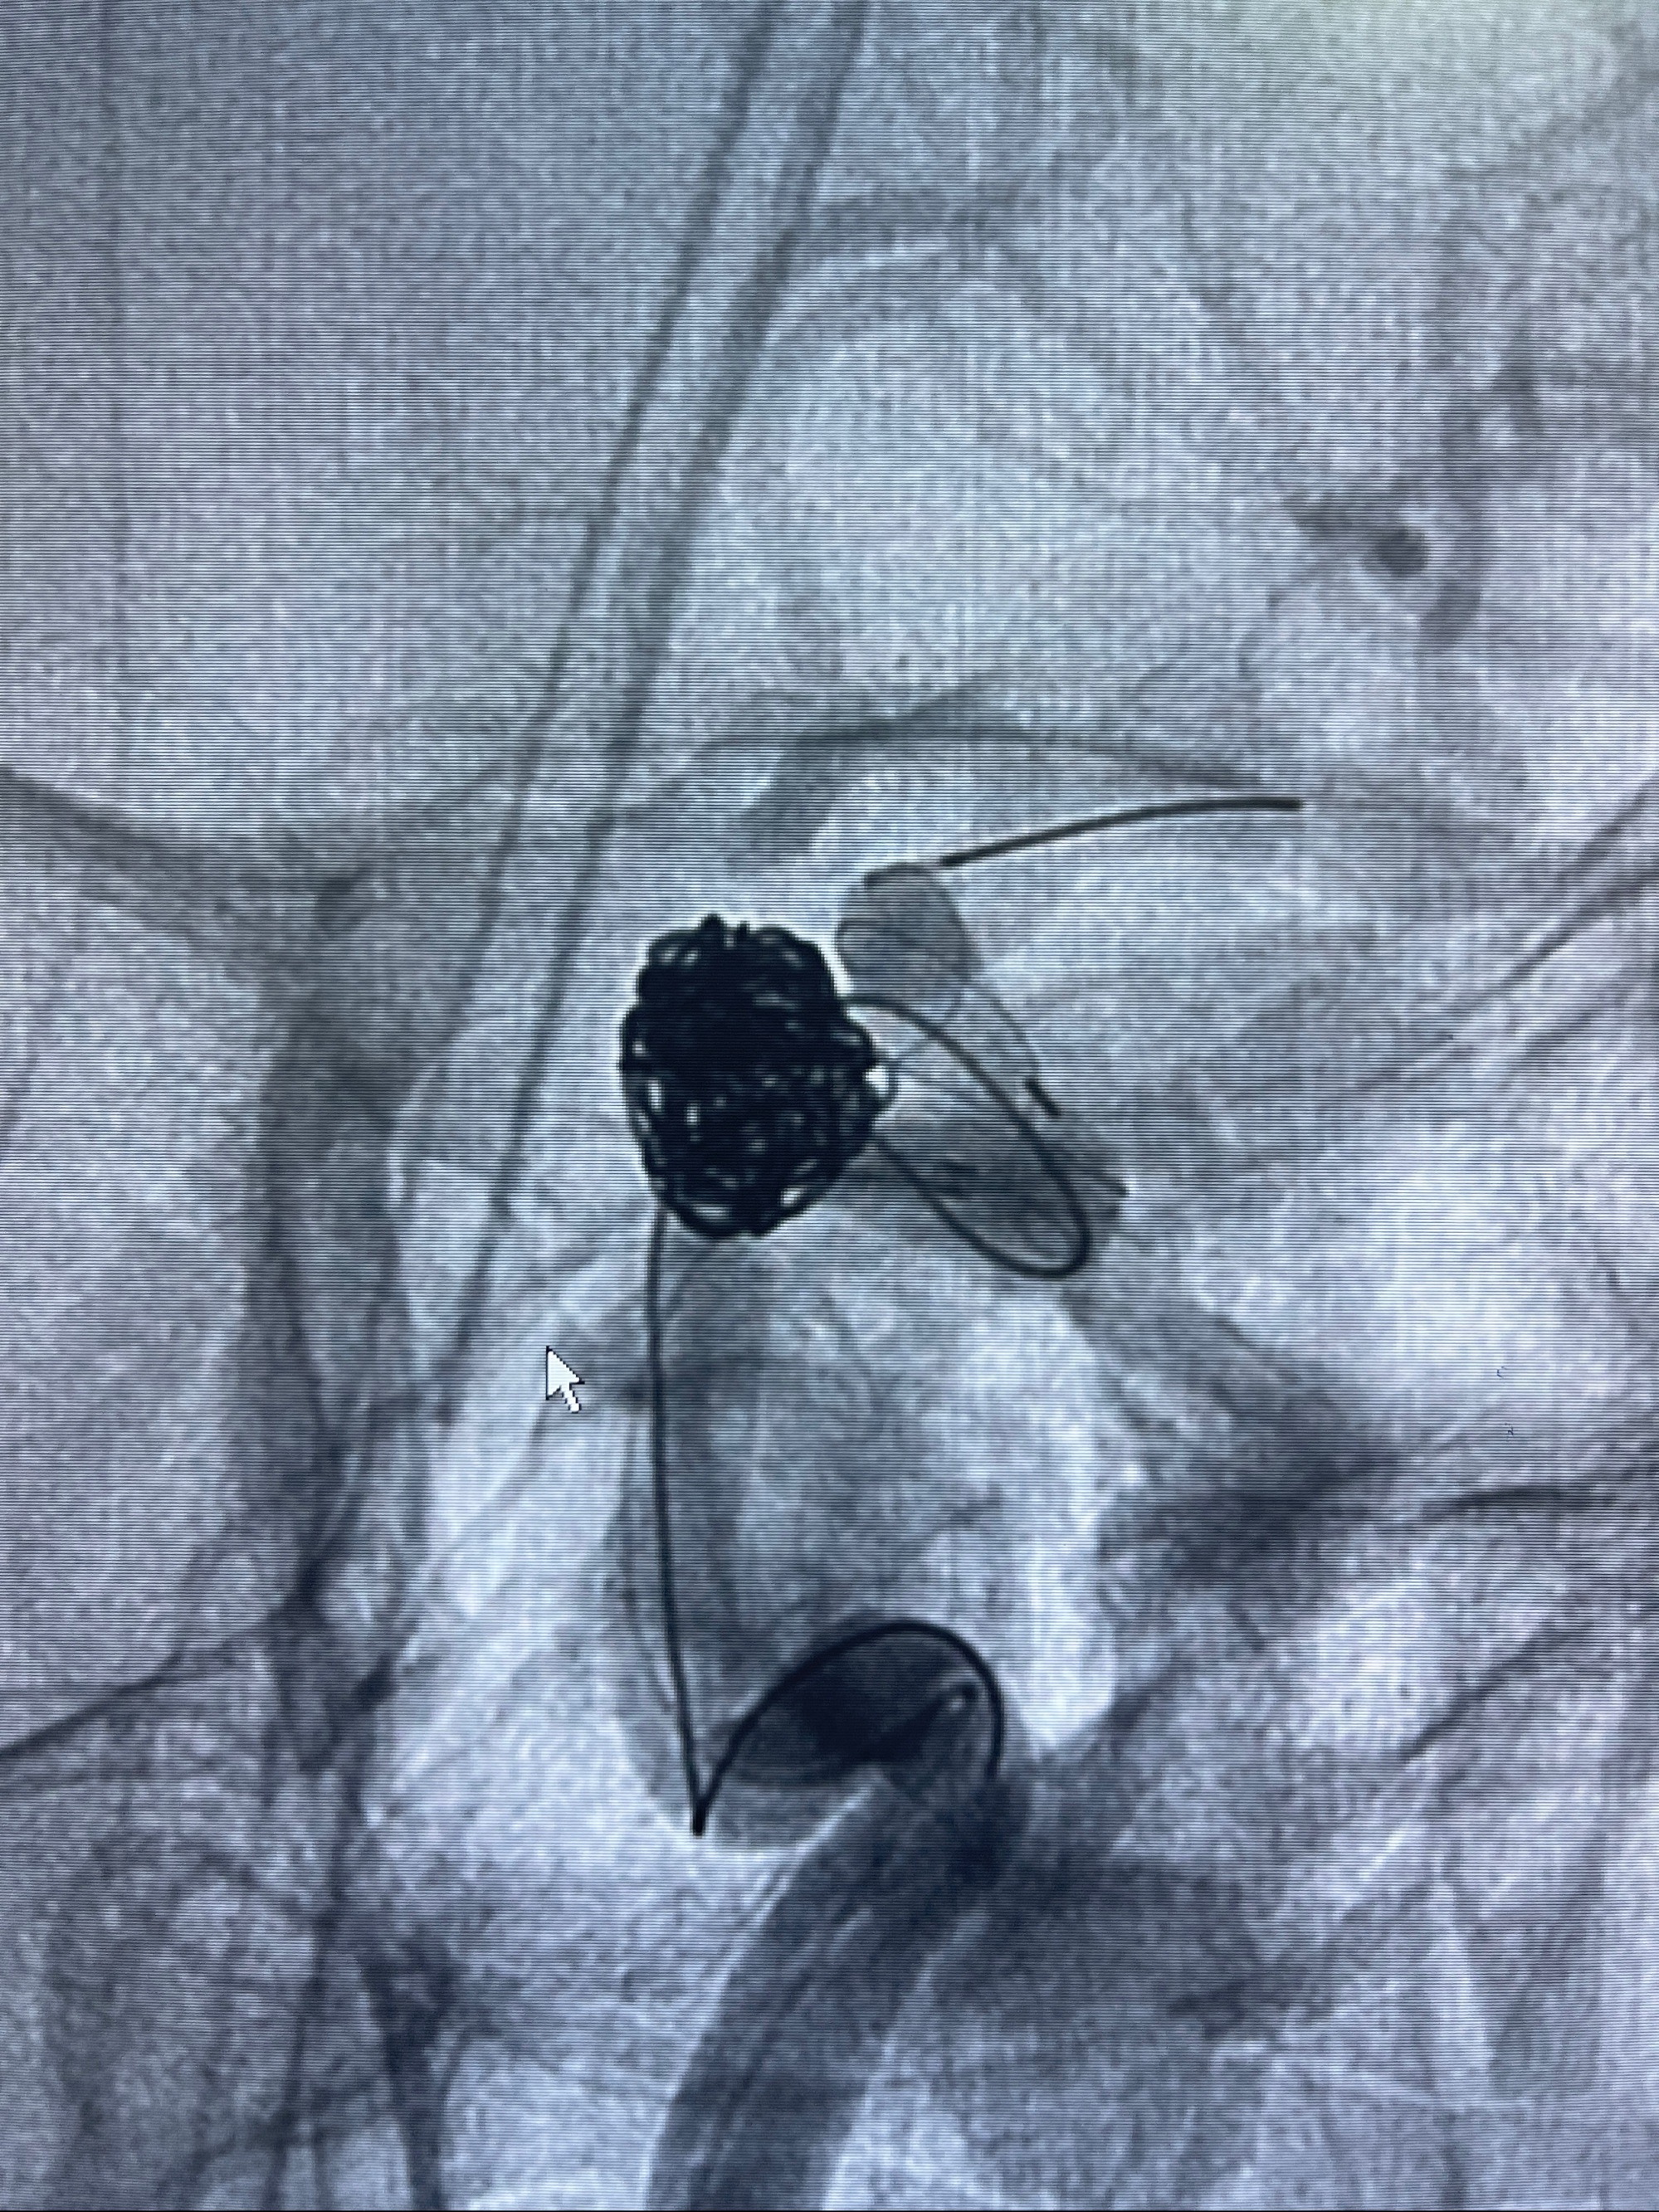

- Tubridge 4.0-20mm密网支架

- 加奇微弹簧圈:7*30/6*20/5*20/2*8

术后3D显示支架贴壁佳

麻醉苏醒佳,遵嘱活动!视力视野正常。